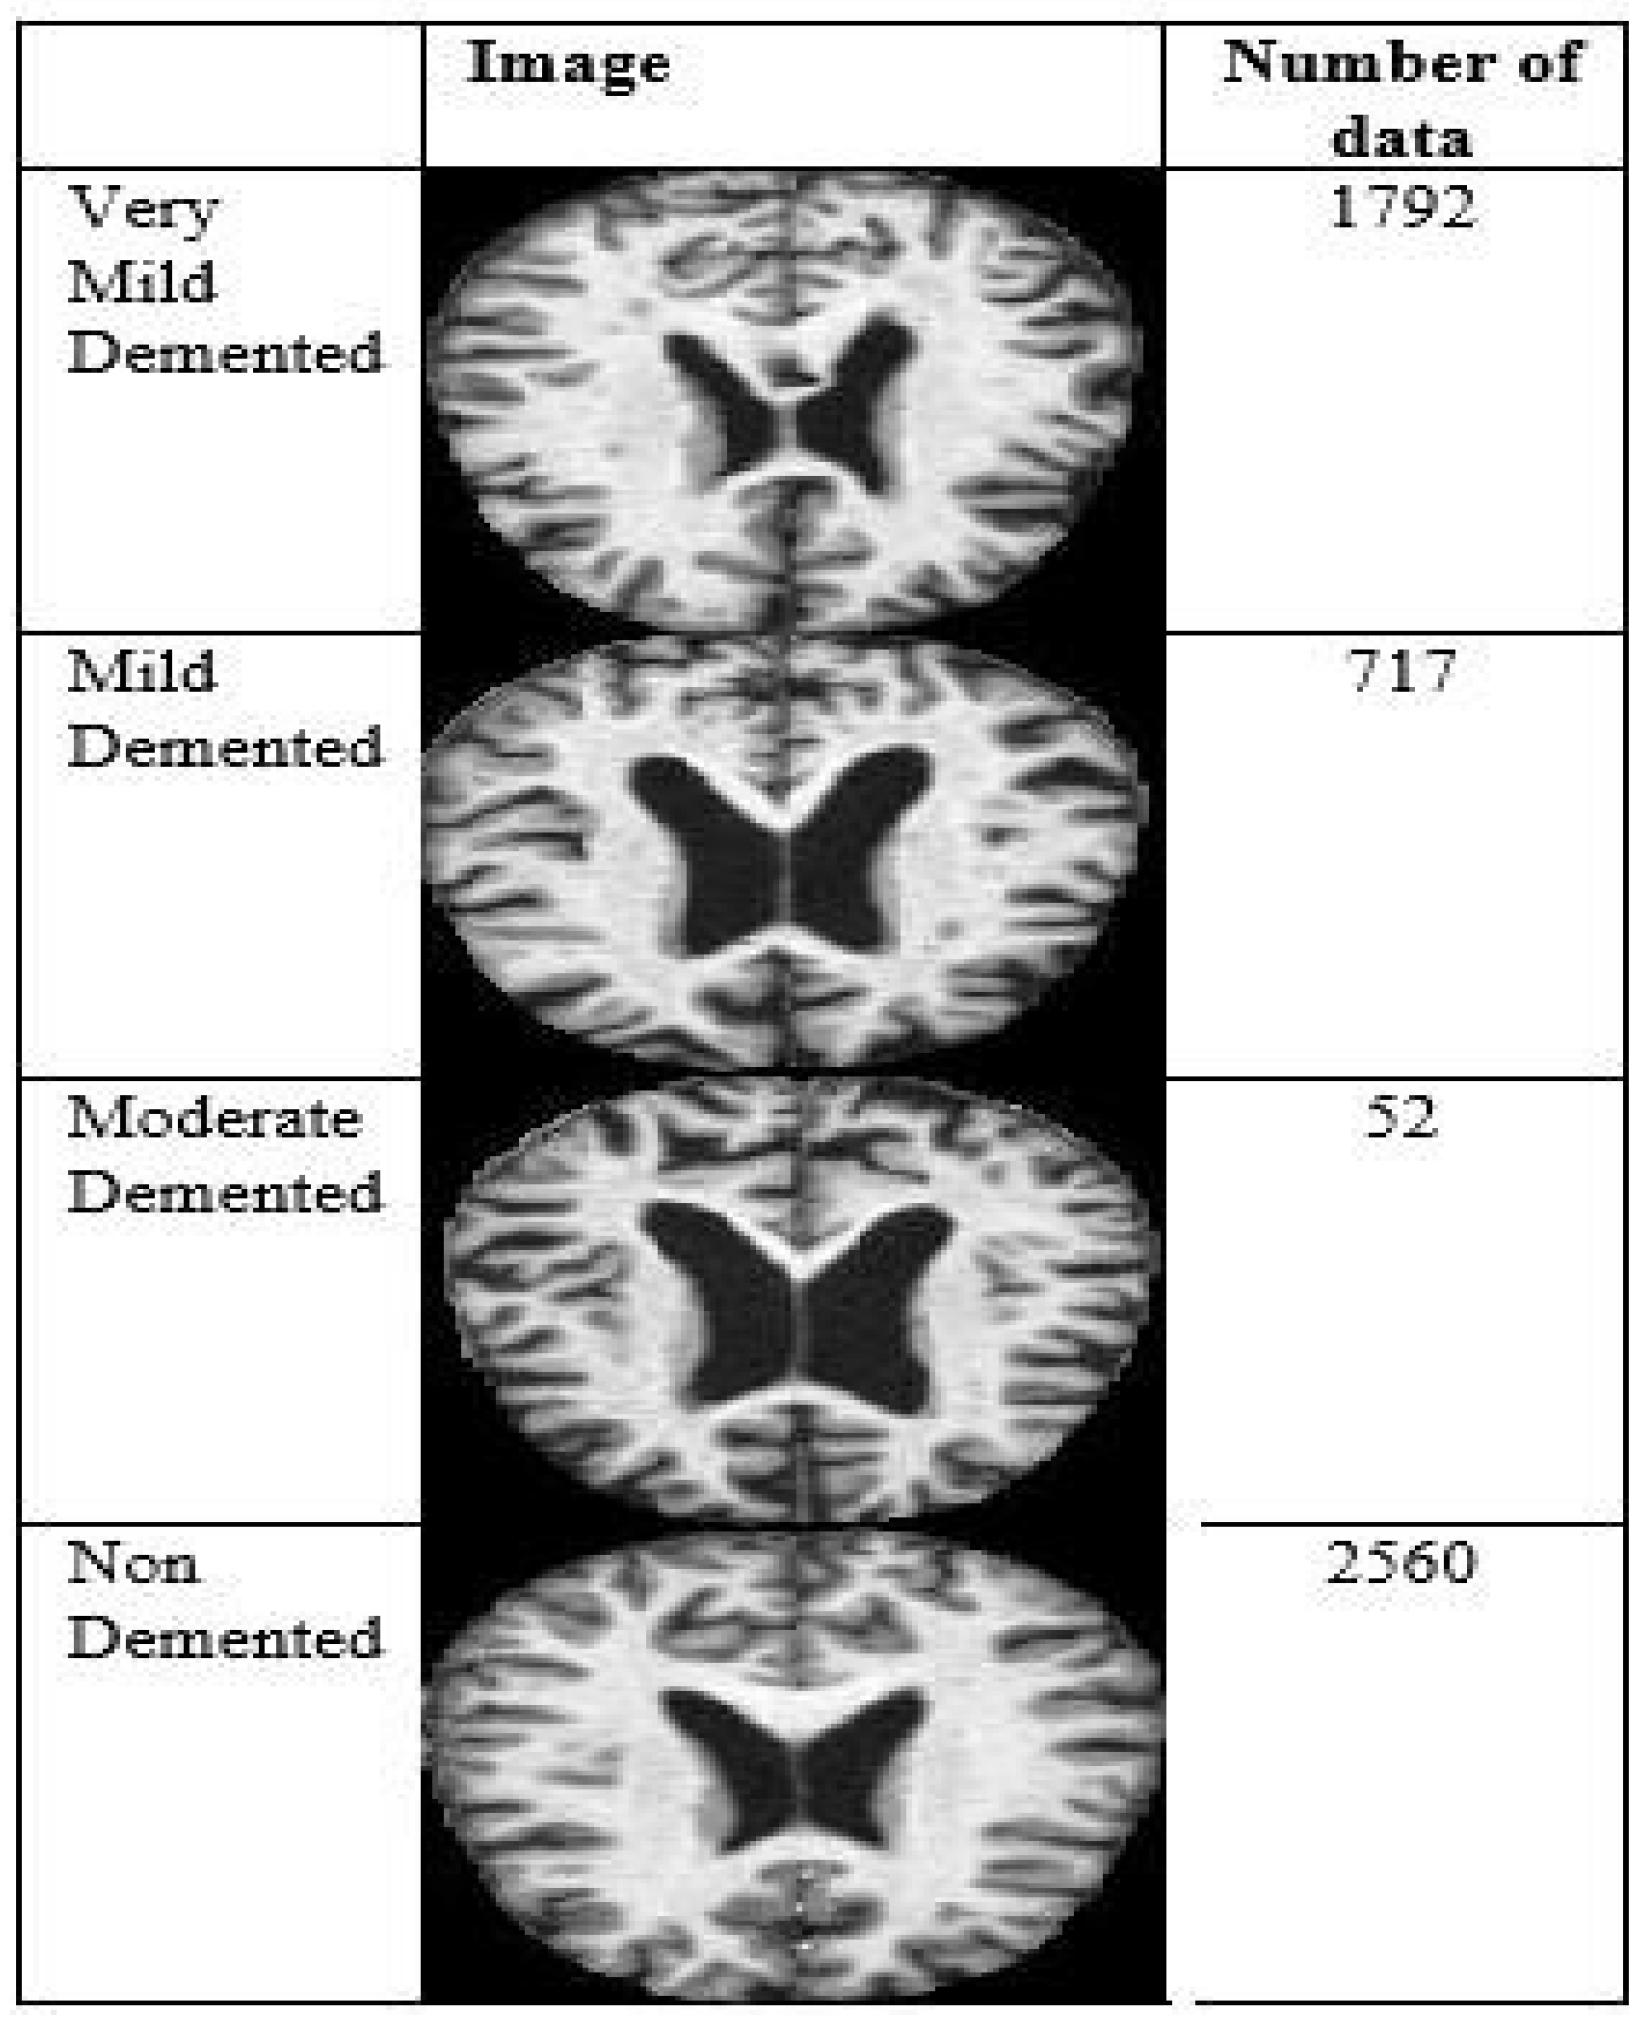

This research used data from Kaggle, a free open-access platform. The study relied on the Alzheimer’s Dataset, which included MRI scans. The following four classes were present in the dataset: very mildly demented, mildly mentally retarded, moderately retarded, and non-demented. Figure 2 shows the amount of data and image samples used in the experiment.

Figure 2. Multi Class Images.